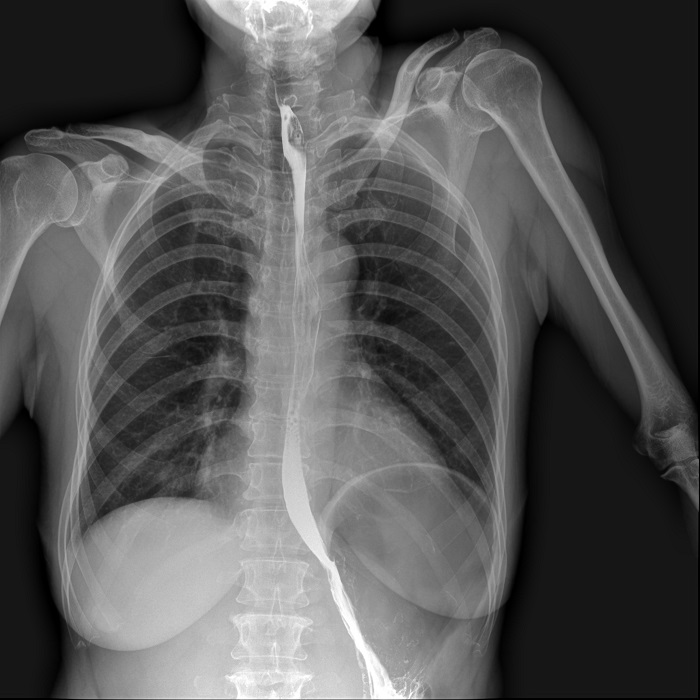

消化道造影高清影像圖片